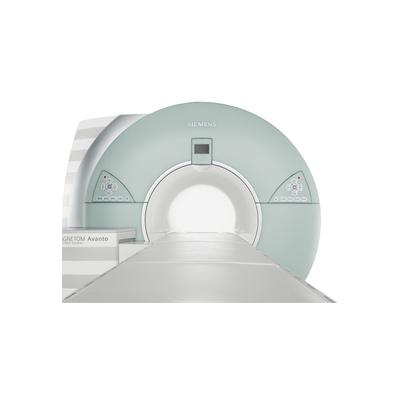

Усовершенственная система MAGNETOM ESSENZA с технологиями Tim+Dot - самый удобный, универсальный и экономически выгодный МР-томограф.

- Повышение производительности с помощью технологий Tim+Dot: более удобный, быстрый и эффективный путь к стабильно высокому качеству изображений;

- Больше приложений для любых областей тела: множество стандартных и дополнительных приложений для расширения спектра медицинских услуг;

- Больше уверенности за счет стабильной экономической отдачи: понятная и надежная структура расходов способствует экономической успешности этого 1,5 Тл томографа.

MAGNETOM ESSENZA 1,5 Tл - система с технологиями Tim+Dot. Данный МР-томограф, разработанный с учетом опыта более чем 1000 пользователей, поможет повысить производительность, универсальность и уверенность в диагностическом результате при повседневной работе МРТ отделения.